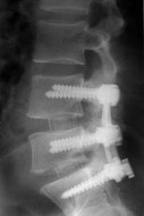

Aspecto final do Raio X após a Artrodese de L4 e L5.